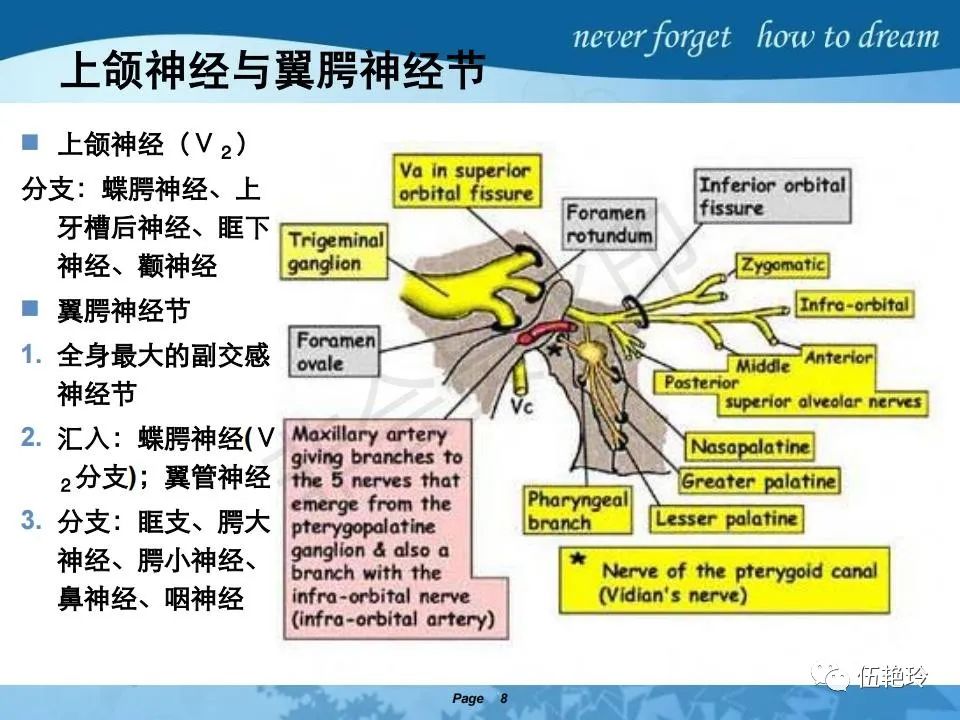

翼腭窝的解剖结构与鼻咽癌侵犯

2.2 鼻咽特有的解剖途径:鼻咽癌原发灶循序进展的总途径:鼻腔(47.8%)→翼腭窝(15.2%)→ 眶下裂(3.2%)→眶尖(1.2%)→海绵窦(0.6%)。

2.31 向上颅内:①鼻咽顶壁→破裂孔(岩尖、斜坡)→蝶窦、海绵窦;②鼻咽顶壁→蝶骨基底部→蝶窦、海绵窦;③鼻咽侧壁→茎突前间隙→蝶骨大翼(卵圆孔)→海绵窦;④鼻咽侧壁→茎突前间隙→翼腭窝→ 颞下窝;⑤鼻咽前壁→鼻腔→翼突、翼腭窝→眶下裂→眶尖→海绵窦;⑥鼻咽前壁→鼻腔→上颌窦、筛窦;